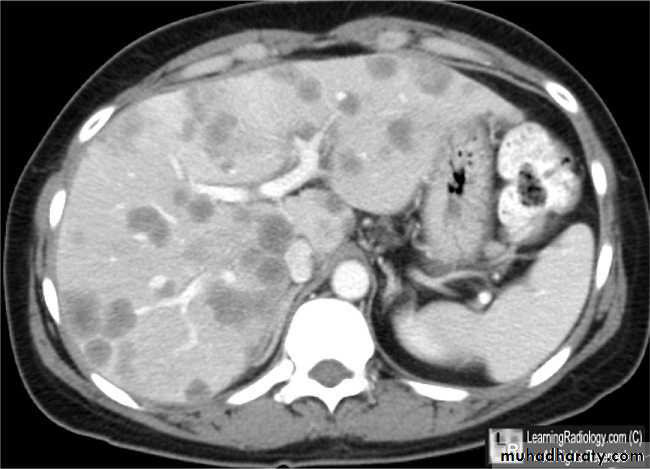

Secondary metastasis in the liver

Multiple rounded hypo density areas of different density , shape & different size .

Pattern of enhancement is either uniform , target or bulls eye pattern .

Hepato megaly .

Secondary metastasis within the liver